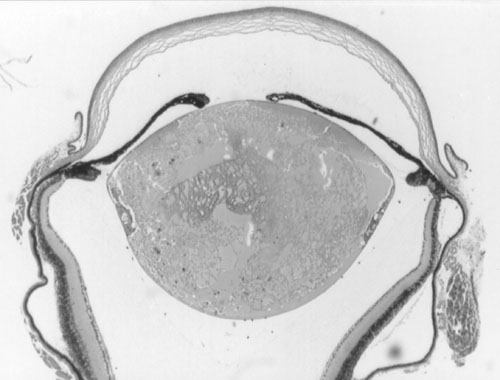

Figure 2. Histology of Ccw/+ eyes

A. Normal littermate 10 days post partum. B. Ccw/+ 10 days post partum. Some vacuolation of the lens is visible. C. Ccw/+ 20 days post partum. Lens fibers are becoming swollen and disorganized. D. Ccw/+ 4-6 weeks post partum. Lens fibers are largely degraded. E. Ccw/+ 14 weeks post partum. Only the lens capsule and some epithelium remain.

C.